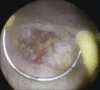

A 85-year-old female patient underwent nephrostomy tube insertion for a huge hydronephrosis due to a papillary mass involving the right ureteral ostium diagnosed by at computed tomography scan. As soon as the nephrostomy tube was inserted, a pulsatile bleeding was found and a renal angiography was done. A massive bleeding from the main and unique right renal artery was found such as to require prompt endovascular embolization. A transurethral resection of the bladder was performed and the pathology report confirmed high-grade pTa transitional cell carcinoma. An open drainage was then placed to empty the contents of the pyelocalyceal system of the kidney. Once obtained the volumetric reduction of the abdominal mass the patient underwent the right nephroureterectomy.